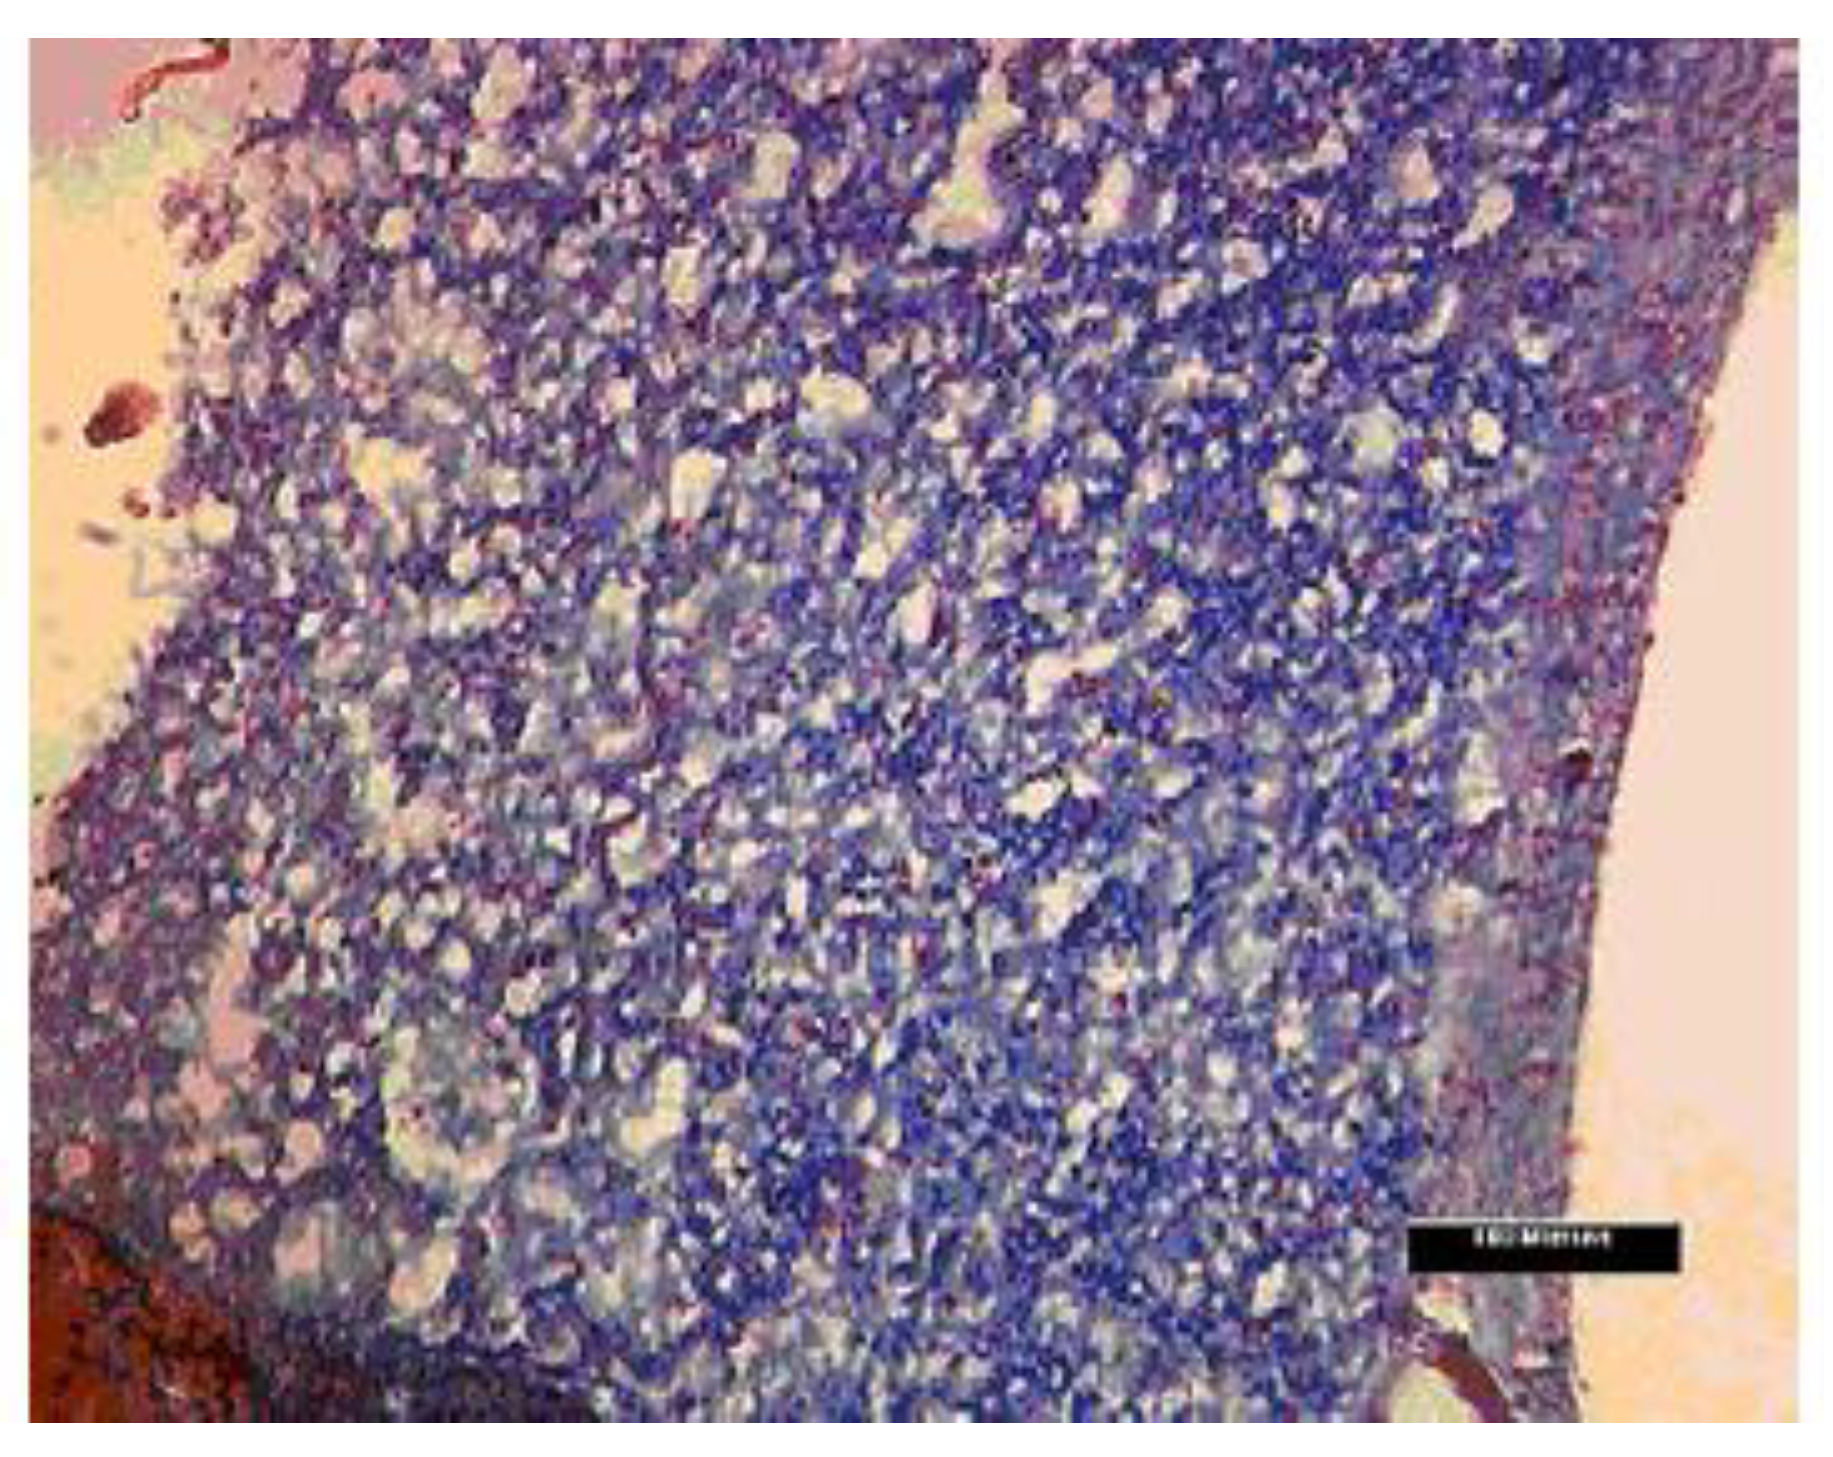

- McManus, M.C.; Boland, E.D.; Simpson, D.G.; Barnes, C.P.; Bowlin, G.L. Electrospun fibrinogen: Feasibility as a tissue engineering scaffold in a rat cell culture model. J. Biomed. Mater. Res. A 2007, 81, 299–309. [Google Scholar] [CrossRef] [PubMed]

- McManus, M.; Boland, E.; Sell, S.; Bowen, W.; Koo, H.; Simpson, D.; Bowlin, G. Electrospun nanofibre fibrinogen for urinary tract tissue reconstruction. Biomed. Mater. 2007, 2, 257–262. [Google Scholar] [CrossRef] [PubMed]